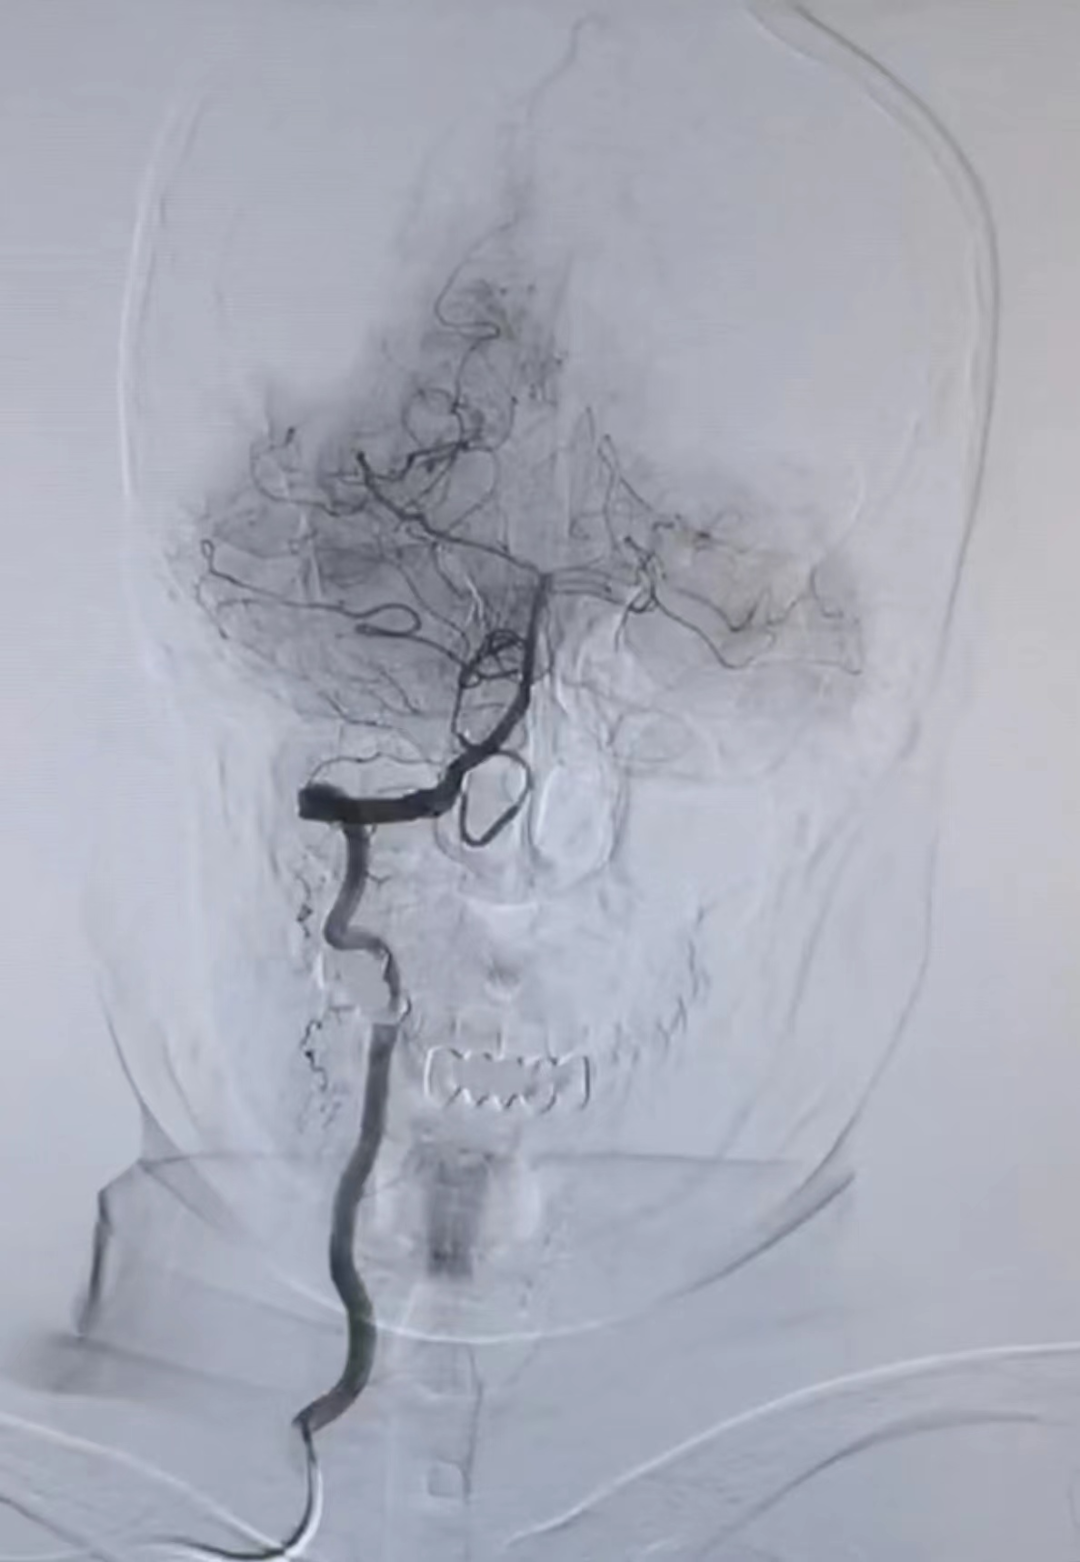

近日,齐医附属一院神经外科二组成功完成医院首例“经桡动脉穿刺行全脑血管造影术”,这标志着我院神经外科脑介入诊疗水平再上一个新台阶。

而桡动脉位于人体腕部,经桡动脉脑血管造影,只需在手腕部的一根血管中引入造影导管,就可进入颈内动脉、锁骨下动脉、椎动脉,完成脑血管造影检查。经此途径实施造影穿刺部位损伤小,出血少,并发症少,术后即可下床活动,舒适度高。

经桡动脉冠状血管造影在心脏介入领域普遍应用,已成为冠状造影的首选入路途径。由于脑血管解剖复杂,迂曲多,因此经桡动脉全脑血管造影术在手术技术方面难度较大,对医生操作要求很高。本院神经外科二组已成功开展此项技术,为广大脑血管病患者开辟了新的检查治疗途径,体现了快速、精准、微创的救治理念。今后,该类手术将积极推广常规开展。

DSA是一种崭新的X线检查新技术。它是先选一入路动脉,一般选用股动脉(常规),亦可选择桡动脉入路(新技术)。通过股动脉或桡动脉放置一动脉鞘,通过该动脉鞘管选用不同导管,在导丝引导下,选进所要显示动脉,注入含碘造影剂。造影剂所经过的血管轨迹连续摄片,通过电子计算机辅助成像为脑血管数字减影造影(DSA)。DSA可清楚地显示脑动脉管腔狭窄、闭塞、侧支循环建立情况等,对于脑出血、蛛网膜下腔出血,可进一步查明导致出血的病因,如动脉瘤、动静脉畸形、动静脉瘘等。目前被公认为血管性疾病诊断的“金标准”。

和临床常用的MRA、CTA相比,DSA不仅可提供直观的颈部和脑血管实时影像,而且可以充分显示从动脉到静脉整个循环过程的周期、形态、分布与走行等动态变化,使临床医师全面了解和判断疾病的可能原因、发病部位、病变程度,以便选择最佳的治疗方式。